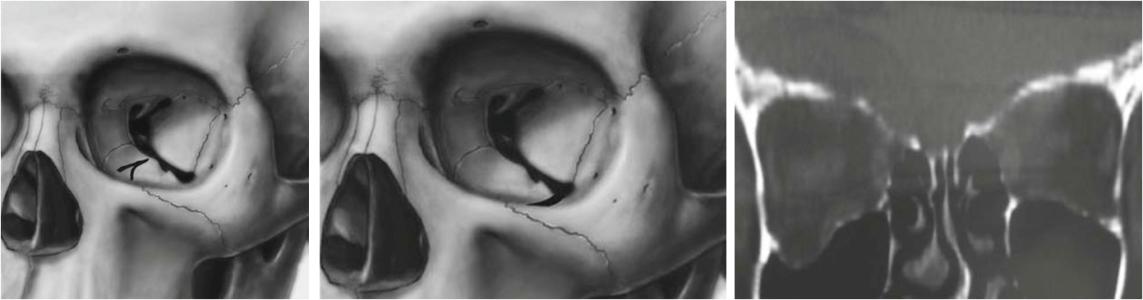

1.眶下壁骨折

是爆裂性骨折最多见的部位。16岁以下患者多为下壁。眶下沟较为薄弱,下壁骨折位置多在此处.或在眶下沟的两侧。虽然眶内壁筛骨纸板比下壁更薄,由于年龄小,眶内壁富有弹性,在外力作用时易产生变形,而不至骨折发生。随着年龄增加,内壁骨折机会增加。

(2)眼球内陷:严重外伤,骨折范围大,嵌顿于上颌窦软组织较多者,伤后立即出现眼球内陷,但大多数发生在伤后10天左右。轻者内陷2—3mm,重者可达5—6mm,睑裂变小。

(4)眼位低:因眶下部脂肪、眼球恳韧带、下直肌和下斜肌疝入上颌窦,致使眼球向下移位。

2.眶内壁骨折

筛骨纸板也是爆裂性骨折多见部位,可以是单纯眶内壁骨折,骨折也可在眶内下角,包括筛骨纸板及上颌窦内侧部分。成年人眶内壁弹性减弱,其内壁最薄,平均0.2~0.4mm,是其好发爆裂性骨折的解剖因素。

(1)复视及眼球运动障碍:内壁骨折特征性表现是水平性复视,眼球外展运动障碍。内壁骨折时,内直肌鞘及软组织嵌入骨折缝内,或内直肌向内移位粘连,限制眼球运动而出现复视。

(2)眼球内陷:由于眶内壁大部分薄弱,因此骨折时多形成骨折片,很少有线状裂隙,由于骨折片移位,眶腔容积增大,相当于眶内壁减压术的作用。这是早期即出现眼球内陷的主要原因。对于伤后晚期出现的眼球内陷,眶内脂肪萎缩是主要原因。